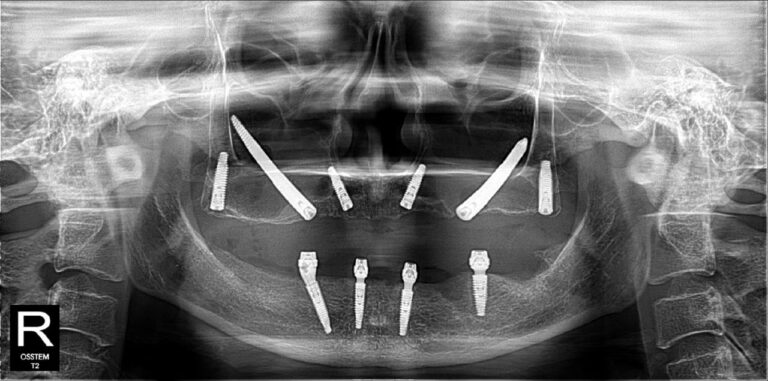

Không nằm ở lời nói mà thể hiện qua kết quả điều trị thực tế. Những hình ảnh X-quang dưới đây là sự khẳng định cho năng lực phẫu thuật và sự chính xác tuyệt đối của BS CKI Nguyễn Trung Khánh trong các ca đại phẫu thuật Implant nhiều lần cắm.

All-on-4/All-on-6 là kỹ thuật phục hồi nhiều răng/toàn hàm bằng cách đặt 4 hoặc 6 trụ implant 1 lần trồng răng